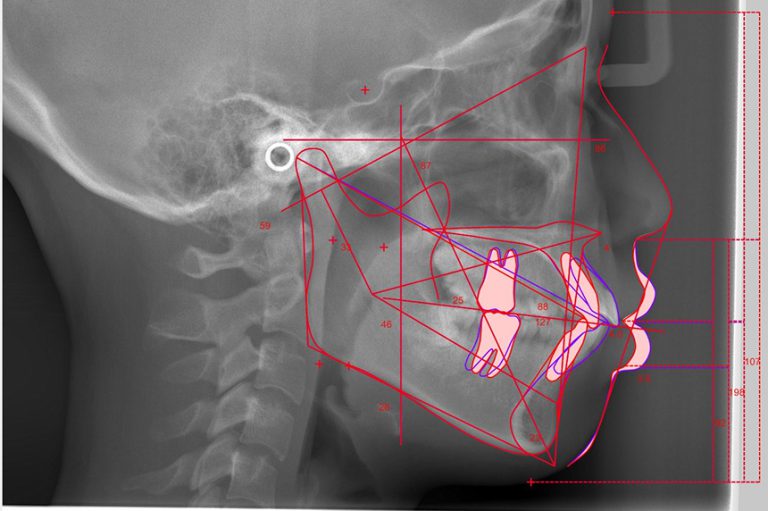

CTや口腔内スキャナー、顔貌の3Dデータをもとに、前歯の出方や傾き、骨格とのバランスまで丁寧に読み解きます。

歯並びや噛み合わせはもちろん、Eラインやスマイルラインとの調和まで見据え、

「どの歯を、どう動かすか」を立体的に設計。